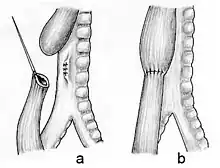

In a minority of cases, the gap between upper and lower esophageal segments may be too long to bridge. In these situations traditional surgical approaches include gastrostomy followed by gastric pull-up, colonic transposition and jejunum transposition.[13] Gastric pull-up has been the preferred approach at many specialized centers, including Great Ormond Street (London) and Mott Children's Hospital (Ann Arbor).[14] Gastrostomy, or G-tube, allows for tube feedings into the stomach through the abdominal wall. Often a cervical esophagostomy will also be done, to allow the saliva which is swallowed to drain out a hole in the neck. Months or years later, the esophagus may be repaired, sometimes by using a segment of bowel brought up into the chest, interposing between the upper and lower segments of esophagus.[15]

In some of these so-called long gap cases, though, an advanced surgical treatment developed by John Foker, MD,[16] may be utilized to elongate and then join the short esophageal segments. Using the Foker technique, surgeons place traction sutures in the tiny esophageal ends and increase the tension on these sutures daily until the ends are close enough to be sewn together. The result is a normally functioning esophagus, virtually indistinguishable from one congenitally well formed. Unfortunately, the results have been somewhat difficult to replicate by other surgeons and the need for multiple operations has tempered enthusiasm for this approach. The optimal treatment in cases of long gap esophageal atresia remains controversial.[17]